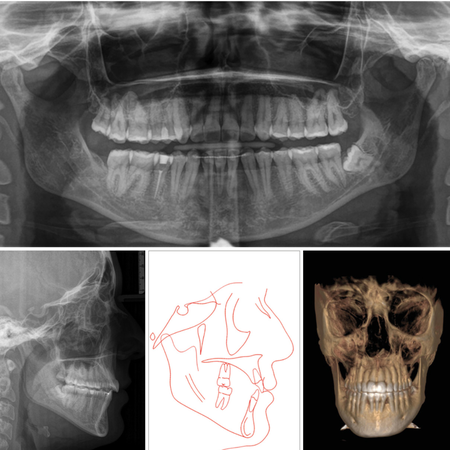

Compensación dentoesquelética extrema para mordida abierta anterior esquelética severa tratada con Invisalign

INTRODUCCIÓN: : La mordida abierta anterior es una maloclusión compleja, a menudo asociada con discrepancias esqueléticas y verticales. Con la evolución de la tecnología de alineadores transparentes, (los alineadores) Invisalign® se han convertido en una opción viable para el tratamiento de casos complejos con una planificación adecuada. CASO CLÍNICO: Este caso clínico describe el tratamiento de una paciente de 28 años con mordida abierta anterior esquelética severa y una...

Extreme dentoalveolar compensation of a severe skeletal anterior open bite with Invisalign®

INTRODUCTION: Anterior open bite is a challenging malocclusion, often associated with skeletal and vertical discrepancies. With the evolution of clear aligner technology, Invisalign® has become a viable option for treating complex cases when appropriately planned. CASE REPORT: This case report describes the treatment of a 28-year-old female patient with a severe skeletal anterior open bite and a slight Class III molar and canine relationship. The treatment involved the use of Invisalign®...